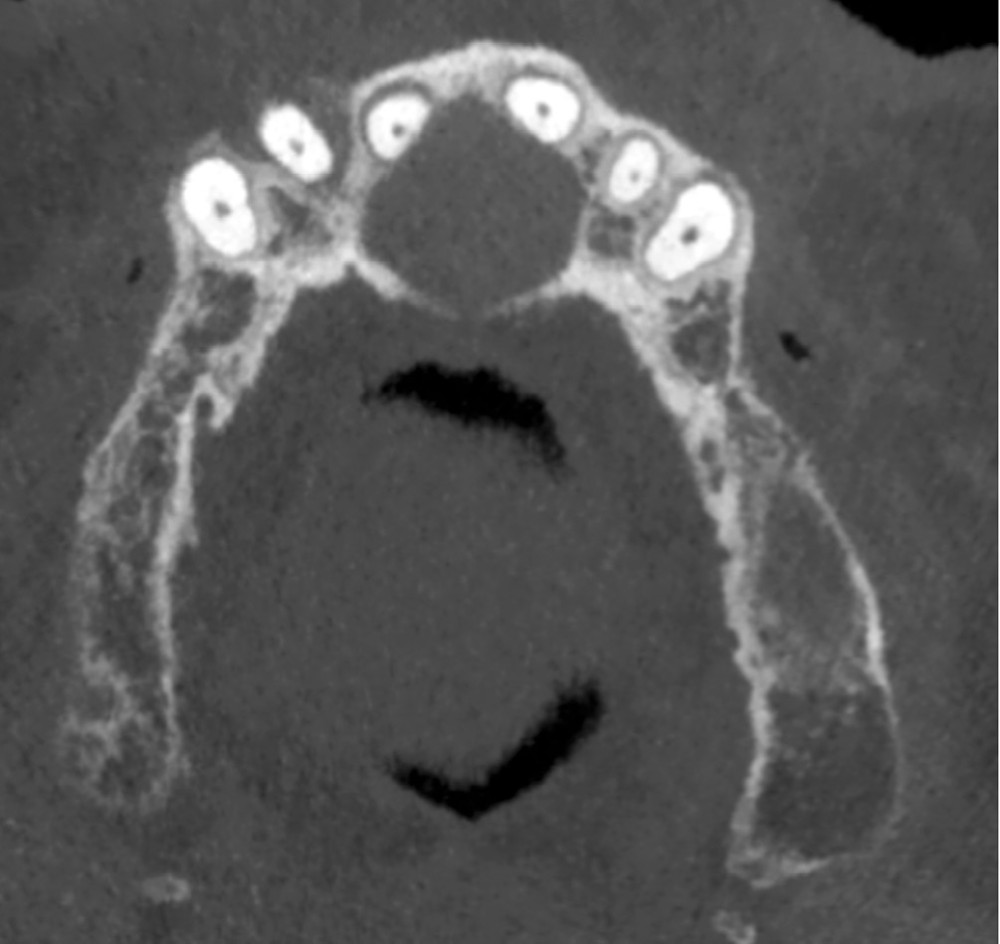

- Uni-loculaire (fig. 3), pouvant présenter un aspect caractéristique de « cœur de carte à jouer ».

- Lorsque le kyste devient volumineux : possibilité de fenestrer la corticale palatine et/ou vestibulaire. Il peut également se développer dans les fosses nasales ou être associé à des résorptions radiculaires (moins de 25% des cas) (fig. 4).

- Plus rarement, extension latérale jusqu’aux prémolaires de façon asymétrique (fig. 5).